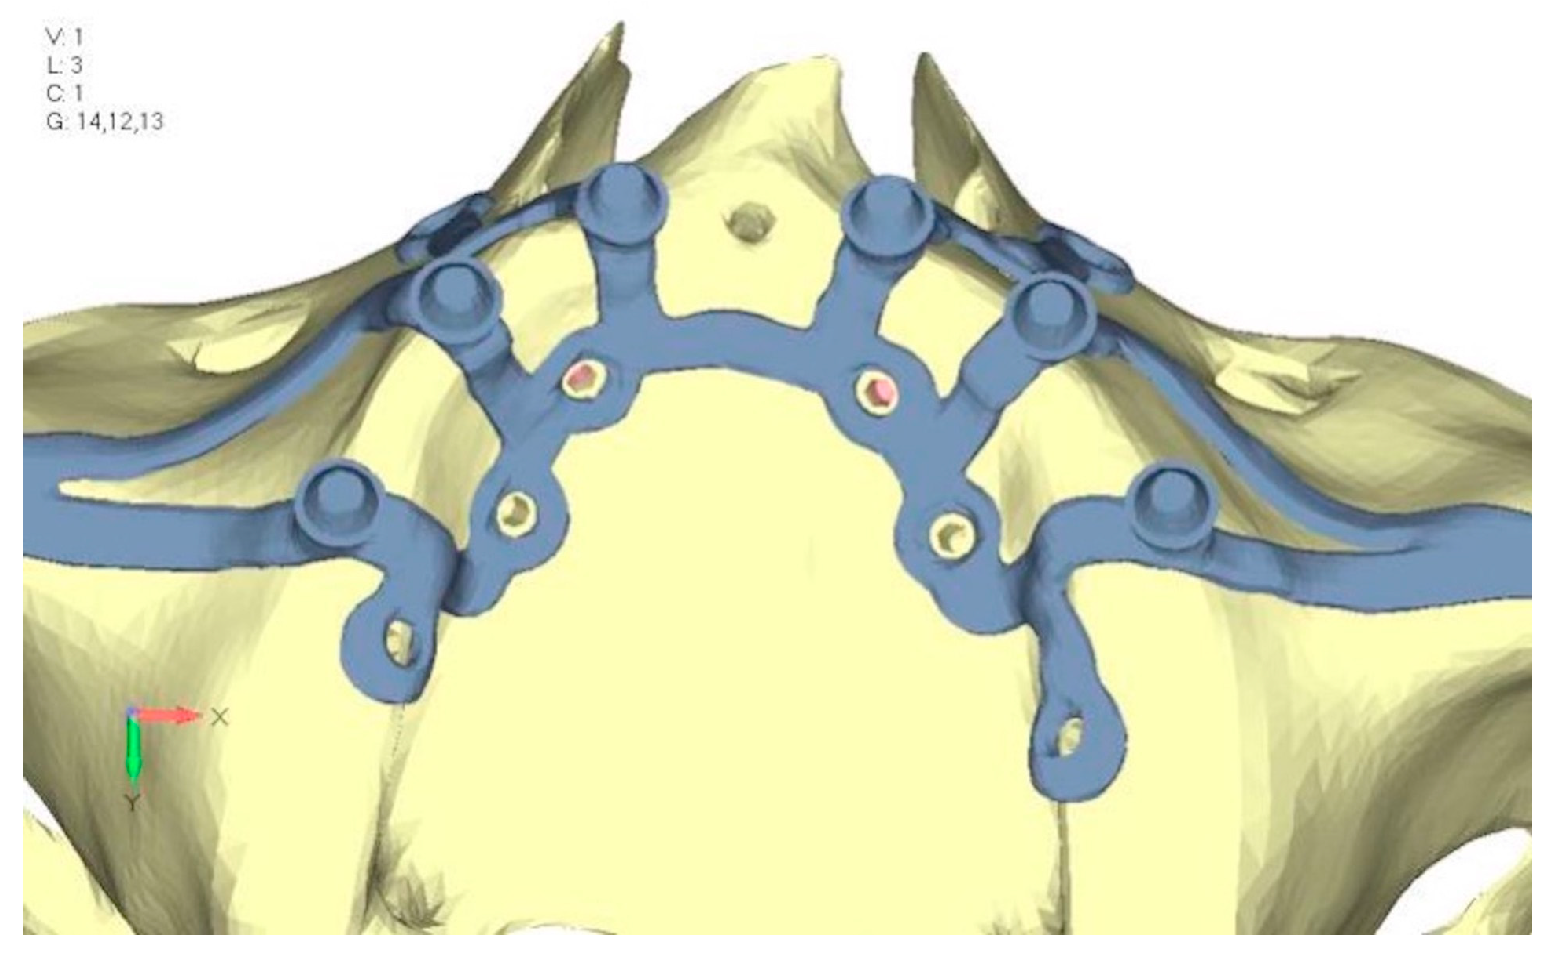

- Model V2. This model serves as an alternative to model V1, as it aims to stabilize the structure posteriorly using screws placed in the vestibular direction rather than the palatal direction (Figure 10). The model displayed similar behavior to V1, leading to the decision to proceed with V1 for further development (Figure 11a,b).